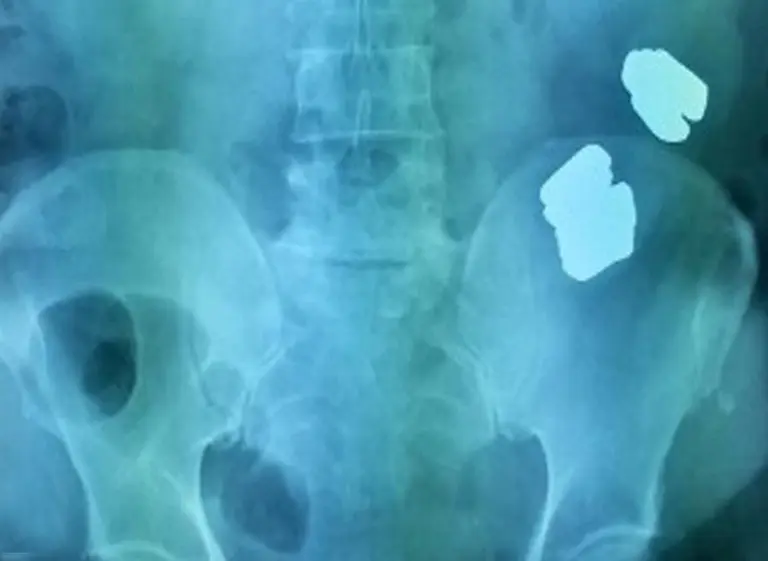

Pero los estudios no coincidían con su versión. "Tampoco podíamos saber que eran barras de oro", dijo el médico. "Pero sí, los rayos X mostraron había bloqueo intestinal, que requería cirugía", agregó. El hospital entregó el metal extraído a la policía local. "Fue algo inesperado", dijo Ramachandran.